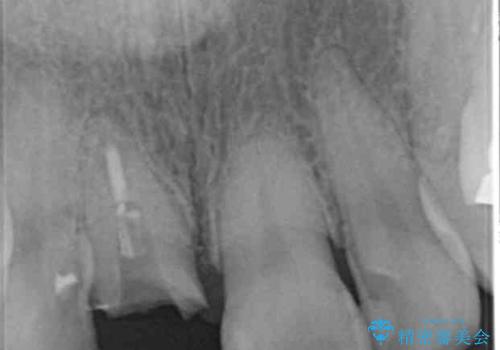

折れてしまった前歯 オールセラミックによる審美改善

- 「野菜をかじった際に前歯がぐらつき、その場で取れてしまった。前歯を入れたい。」と希望され来院されました。

残っている歯質(歯の量)は非常に少ないものの、歯を抜かずに残したい希望が強く、また破折リスクが高いことも

ご理解いただいた上で歯を残しセラミック治療を計画します。

破折リスクを少なくするため前歯でかじったり硬いものを噛み切る等の行為は避けた方が良いとお伝えし、現状5年問題なく経過しています。